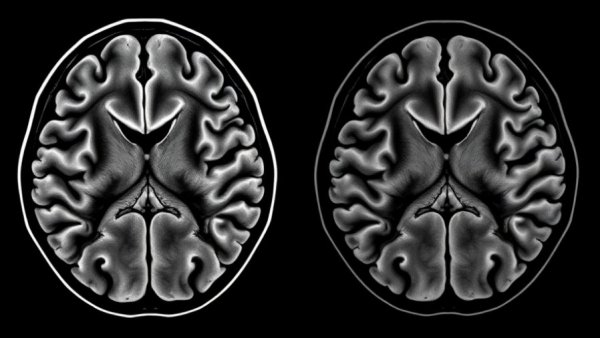

MRI scans showing brain microbleeds linked to sleep apnea.

Sleep apnea is a common yet serious sleep disorder characterized by repeated interruptions in breathing during sleep. In particular, obstructive sleep apnea (OSA) threatens more than just a good night’s rest. Recent research from Korea University Ansan Hospital reveals a troubling link between moderate to severe OSA and an increased risk of cerebral microbleeds. These microbleeds are not only markers of brain damage but have also been associated with cognitive decline, strokes, and dementia.

The comprehensive study analyzed data from a cohort of 1,441 adults over eight years, using sophisticated methods including polysomnography and MRI scans to investigate the relationship between sleep apnea severity and incident cerebral microbleeds.

Results highlighted staggering cumulative incidence rates of cerebral microbleeds: 7.25% for moderate to severe OSA, compared to 3.33% for those without OSA and 3.21% for those with mild OSA. This clearly indicates that the severity of sleep apnea correlates significantly with the risk of developing these dangerous microbleeds.